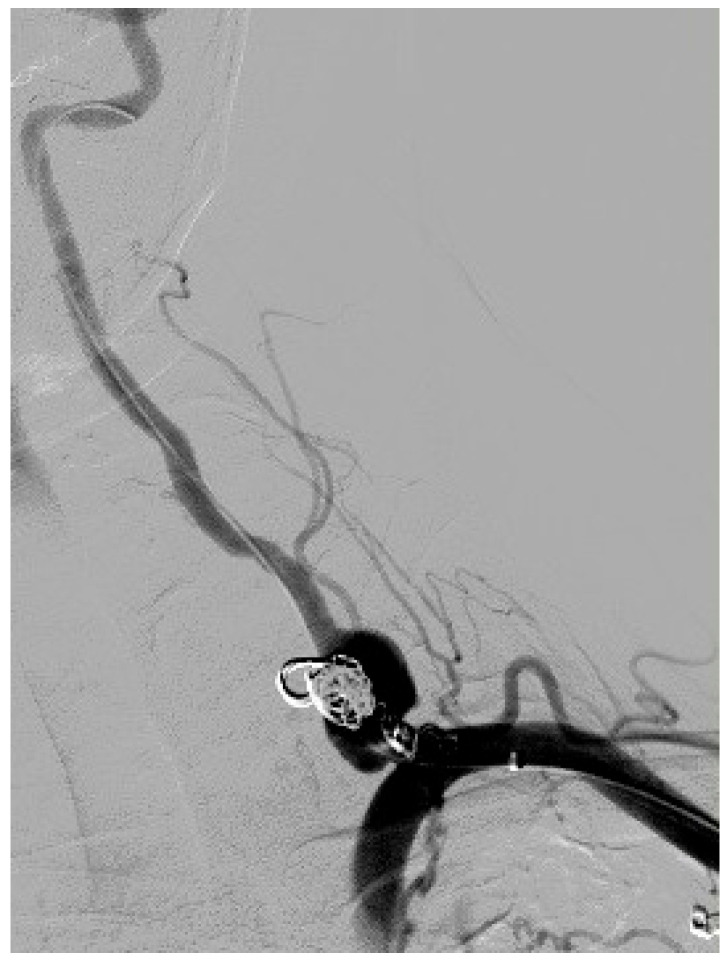

Case presentation: We present the case of a 33-year-old woman in the puerperium with neurofibromatosis type 1 who had a vertebral symptomatic artery aneurysm. During a previous hospitalization, two months before the treatment of the vertebral aneurysm, a same-sided aneurysm of the thyrocervical trunk was successfully treated with endovascular coiling because of aneurysm rupture. In this case report, the vertebral artery aneurysm was successfully managed using a flow diverter stent graft.

Conclusions: This is the first reported case of a successfully treated symptomatic vertebral artery aneurysm with a flow diverter stent graft in a patient with neurofibromatosis type 1 during the early puerperium. Endovascular treatment with a stent graft is a minimally invasive, safe, and effective treatment for patients with vertebral artery aneurysms. Early diagnosis of non-ruptured vertebral artery aneurysms is a crucial as well as appropriate treatment, which should be undertaken in a timely manner to prevent serious complications or a fatal outcome.